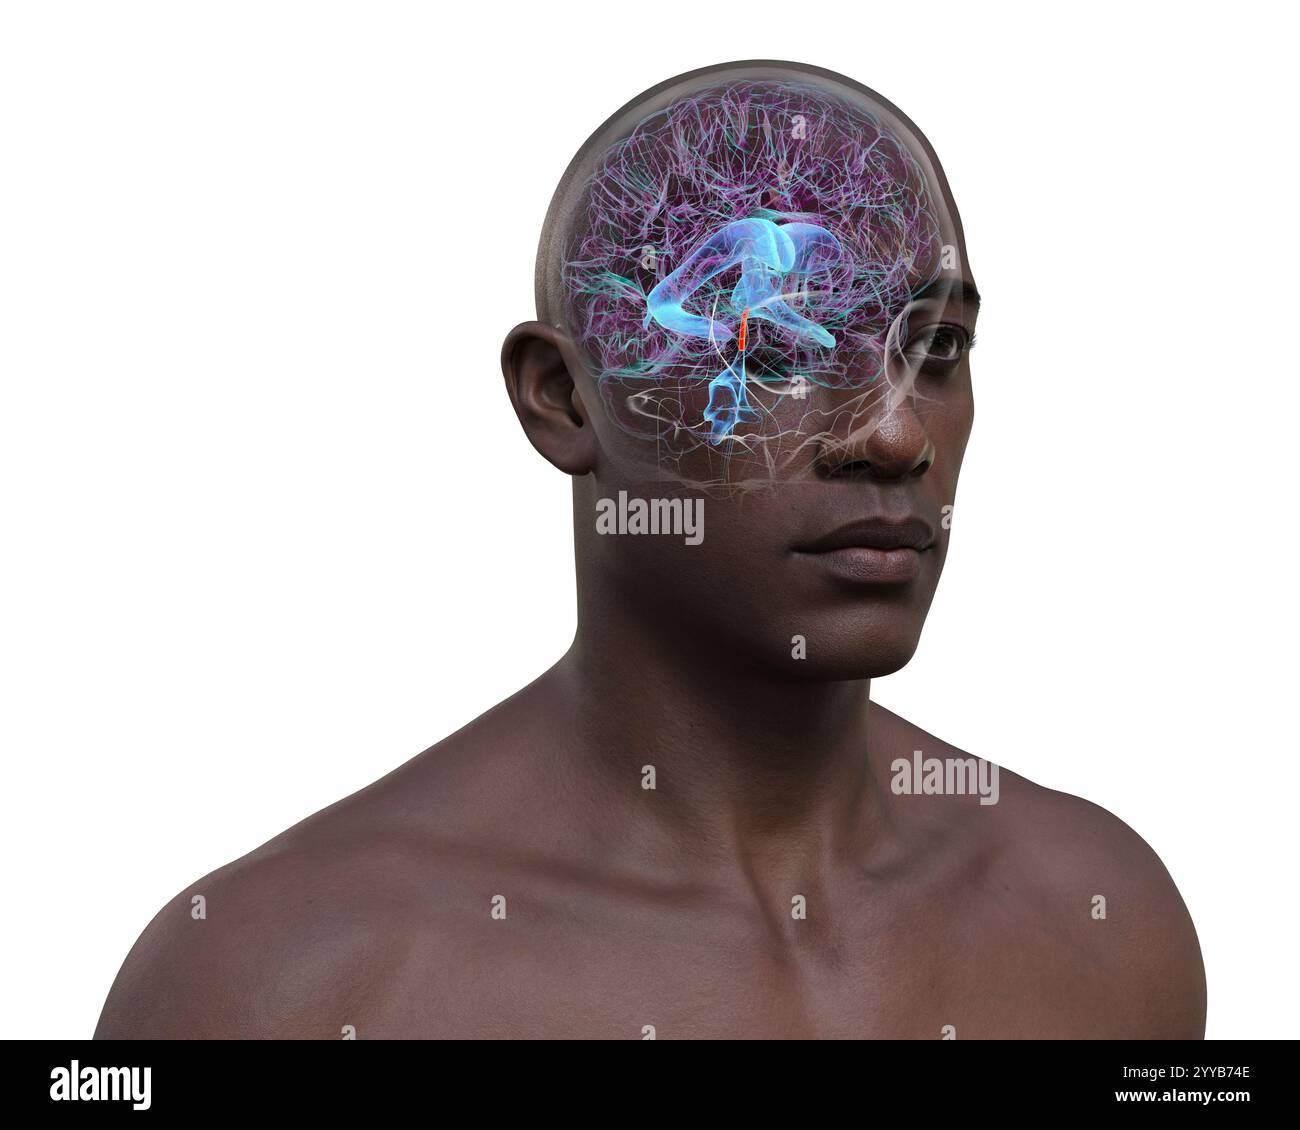

RF2YYB746–Computerdarstellung des menschlichen Gehirns mit orangefarbenem Aquädukt und grünem Ventrikelsystem mit Liquorfluss.

RF2YYB74E–Computerdarstellung des menschlichen Gehirns mit orangefarbenem Aquädukt und grünem Ventrikelsystem mit Liquorfluss.

RF2YYB751–Computerdarstellung des cerebralen Aquädukts (orange), eines schmalen Kanals im Mittelhirn, der den dritten und vierten Ventrikel verbindet und den Liquorfluss erleichtert.

RF2YYB741–Computerdarstellung des menschlichen Gehirns mit orangefarbenem Aquädukt und grünem Ventrikelsystem mit Liquorfluss.

RF2YYB742–Computerdarstellung des menschlichen Gehirns mit orangefarbenem Aquädukt und grünem Ventrikelsystem mit Liquorfluss.